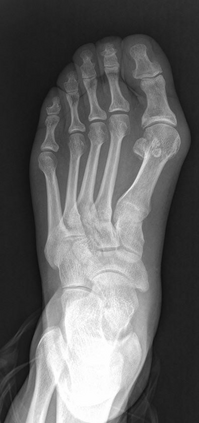

Angular measurements is essential to make a resonable treatment for Hallux valgus (HV), a common forefoot deformity. However, it still depends on manual labeling and measurement, which is time-consuming and sometimes unreliable. Automating this process is a thing of concern. However, it lack of dataset and the keypoints based method which made a great success in pose estimation is not suitable for this field.To solve the problems, we made a dataset and developed an algorithm based on deep learning and linear regression. It shows great fitting ability to the ground truth.